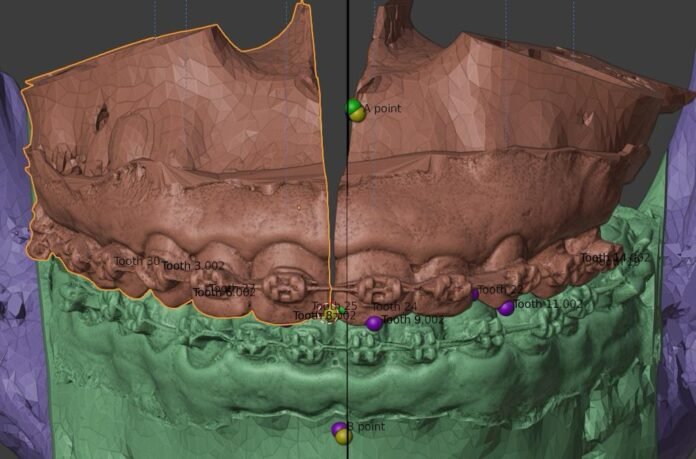

Em 2024, a especialidade de bucomaxilofacial recebeu uma poderosa ferramenta para facilitar o planejamento das cirurgias de alta complexidade. Atualmente, a área conta com equipamentos de impressão 3D que ajudam a criar modelos em tamanho real da parte óssea da face dos pacientes que precisam ser submetidos à cirurgia de reconstrução. A doação dos equipamentos foi feita pelos próprios profissionais da área, que se organizaram para custear a aquisição.

O uso das impressoras 3D para a impressão destes modelos, lembra Ricardo Coelho, torna a execução cirúrgica mais rápida e precisa, diminuindo o tempo cirúrgico e até mesmo de internação do paciente, reduzindo, portanto, o custo geral de todo o procedimento. “É uma forma, inclusive, de liberar leitos com mais agilidade, para que mais pacientes possam receber atendimento mais prontamente”, explica.

Com o uso de softwares de planejamento virtual e impressão 3D, o ambulatório consegue reduzir o tempo de preparação para as cirurgias, aumentando a eficiência e diminuindo a espera dos pacientes na fila cirúrgica. “O laboratório 3D tem sido essencial para agilizar o planejamento para as cirurgias, já que com ele é possível transformar o processo, que antes levava dias, em um trabalho de apenas algumas horas”, complementa o médico.